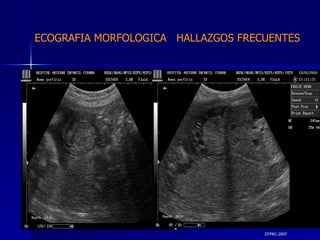

DTFRC-2007 ECOGRAFIA MORFOLOGICA  HALLAZGOS FRECUENTES   MATERIAL Y METODO ES UN ESTUDIO DESCRIPTIVO, RETROSPECTIVO  DE ESTUDIO ECOGRA FICOS REALIZADOS ENTRE MARZO 07 A MARZO 08 EQUIPO DE ALTA RESOLUCION   VOLUSON 730 PRO  MEDISON SA 8000 live MEDISON SA 8000SE CRITERIO DE INCLUSION:   POBLACION GENERAL    GESTACIONES  20 a 24 SEMANAS   UNIVERSO  N 211

DTFRC-2007 ECOGRAFIA MORFOLOGICA  HALLAZGOS FRECUENTES   Sistema Nervioso Central  8  Cardiovascular  0 Genitourinario  6 Musculos Esqueleticos  2 Gastrointestinales  2  Otros  12  Total  30   NUMEROS DE ANOMALIAS POR SISTEMA n N  211

DTFRC-2007 ECOGRAFIA MORFOLOGICA  HALLAZGOS FRECUENTES   SISTEMA NERVIOSO CENTRAL TOTAL  8  26 % 1 HIDROCEFALIA 2 VENTRICULO MEGALIA 4 QUISTE DE PLEXO COROIDEO 1 ANENCEFALIA